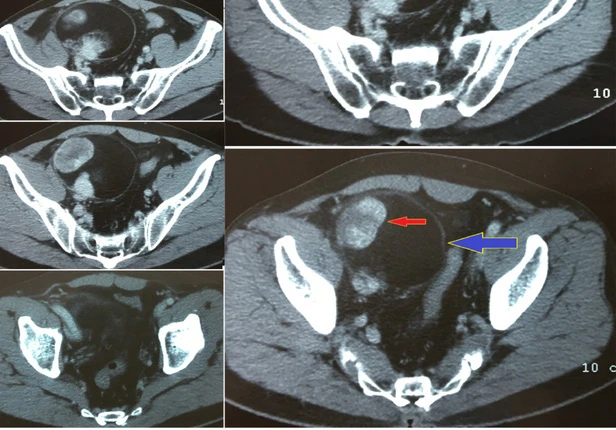

Hình ảnh CT scan của bệnh nhân được các bác sĩ của BV Nhân dân Gia Định xem và đánh giá nhanh ngay trong phòng mổ. Ảnh: CTV